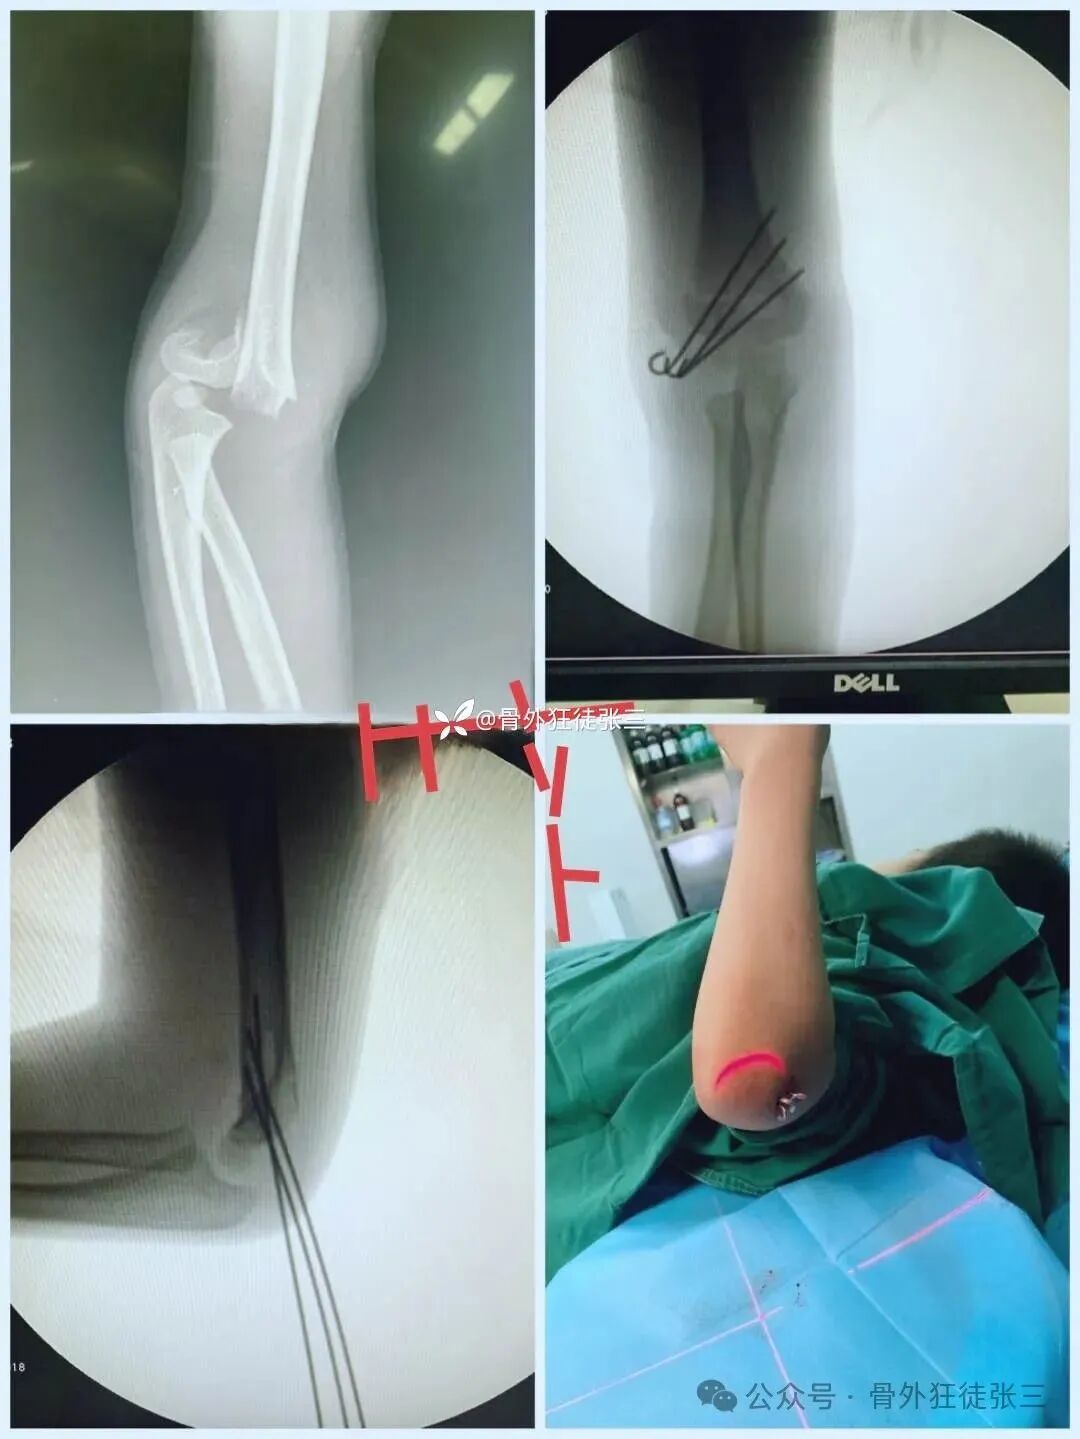

病例4,髁上骨折

(以下髁上骨折,术后处理方案同方案1)

病例12,交叉针

6年前最开始做闭合穿针时固定方式

后来因为出现过一例医源性尺神经损伤

百分之百确保打针没有穿到尺神经

术后查房却发现环小指屈曲畸形,伸直受限

立即拔针后逐渐恢复

考虑可能穿刺形成血肿或者肿胀后压迫尺神经所致

后来发现

桡侧三枚针

发散固定

能解决大部分骨折类型

偶尔有尺侧柱不稳定的病历

需要从尺侧进针

病例13,交叉针,桡侧2枚,尺侧1枚